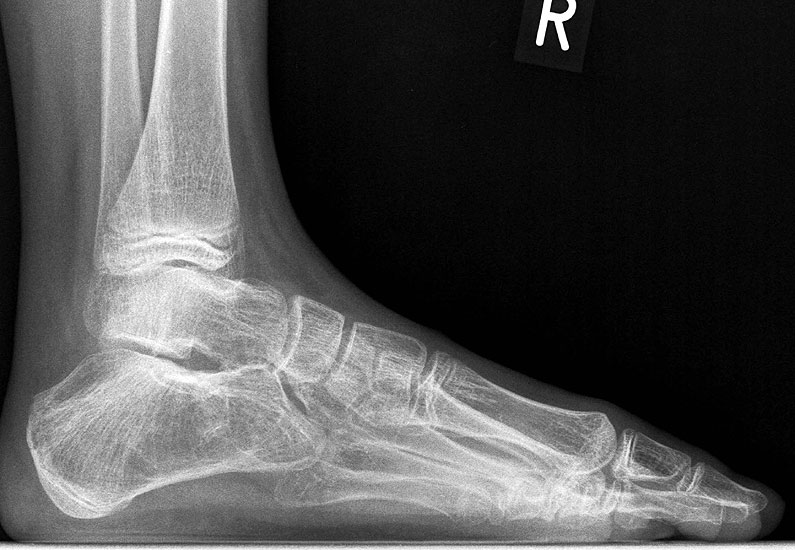

Z.n. Distorsion des Fußes mit „Ruptur“ der (vorbestehenden) talocalcanearen Coalitio. Die Wassereinlagerung in den an die Coalitio angrenzenden knöchernen Bezirken ist im MRT gut zu erkennen. Nach monatelangen Beschwerden spontane Besserung.

Abbildung 1

• Anhaltende Schmerzen nach vermeintlichen oder tatsächlichen Distorsionen („Aktivierung“ der Coalitio, vgl. Abb. 1)